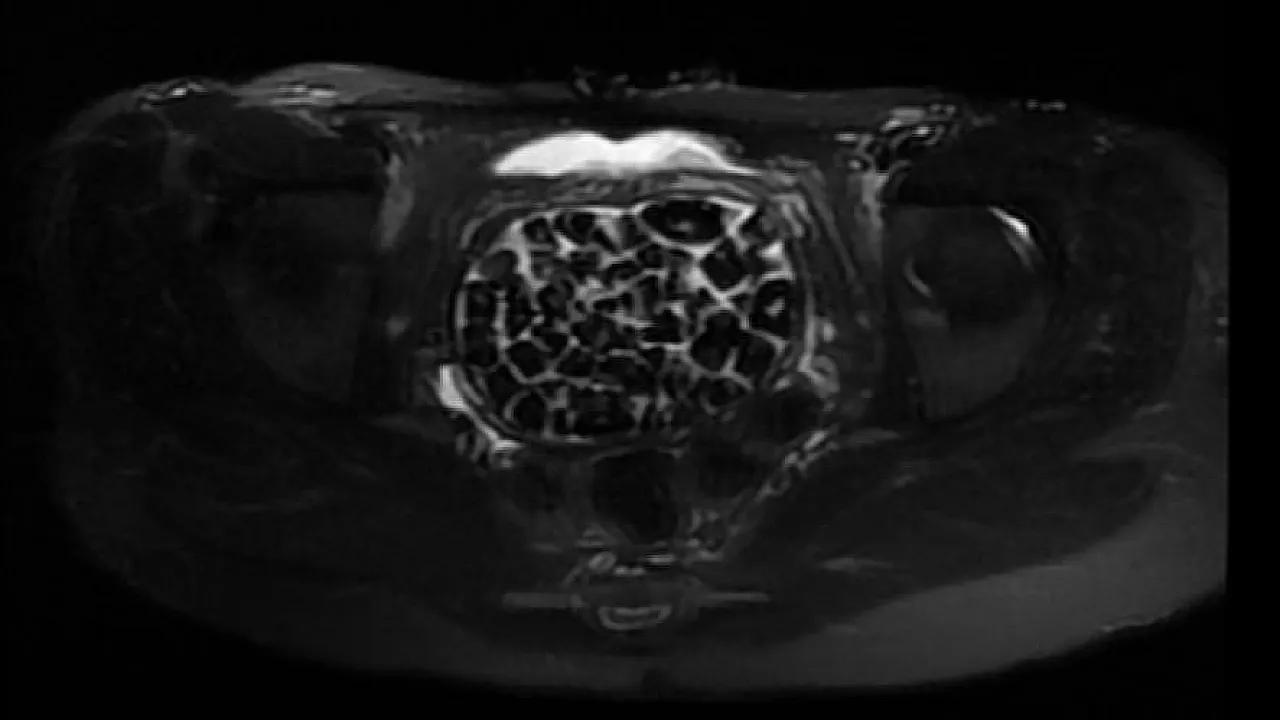

Ameliyatı gerçekleştiren Üroloji Uzmanı Doç. Dr. Erkan Erkan, hastanın geçmişte art arda ameliyatlar geçirdiğini ve yapılan görüntülemelerde mesane arkasında taşlarla dolu bir kese tespit ettiklerini belirtti. Ek görüntülemelerle taşların vajinal boşlukta oluştuğu kanaatine varıldığını ifade eden Erkan, operasyon sırasında toplam 287 taşın çıkarıldığını ve bunun literatürde son derece nadir görülen bir durum olduğunu vurguladı.

Jinekolojik Onkoloji Uzmanı Op. Dr. Emin Erhan Dönmez ise hastanın uzun süredir karın ağrısı şikayetiyle geldiğini, yapılan muayenede vajen bölgesinde göllenen idrar nedeniyle taş oluştuğunun tespit edildiğini aktardı. Dönmez, mesaneden vajene geçiş sırasında tüm vajenin taşlarla dolu olduğunu gördüklerini ve en büyüğü 2,5 cm olan 287 taşın çıkarıldığını belirtti. Bu kadar yüksek sayıda taşla karşılaşmanın kendileri için de şaşırtıcı olduğunu ifade eden Dönmez, vakayı literatürde benzeri olmayan bir örnek olarak değerlendirdi.